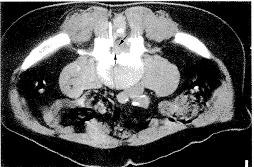

本组病例在CT或带影像增强器的X光机导引下进行穿刺,采用背后入路的方法直接穿刺椎间盘脱出部位(一种新的盘外穿刺方法)。穿刺针使用7号腰穿针,长16 cm、针尖前端略弯曲。选择棘突间间隙为进针点,CT导引下直接穿刺突出的软组织影。或在带影像增强器的X光机导引下进行穿刺,先正位透视大概确定突出部位的穿刺方向,然后侧位透视确定穿刺针的深度,进针过程中针尖缓慢穿过椎管的前后硬脊膜,直至针尖到达椎体的后缘,然后注射少许的Isovist(一种非离子型造影剂,先灵药业有限公司生产)了解突出的椎间盘组织是否显影,调整针尖准确位置后,往脱出部分的椎间盘组织注射600单位的胶原酶溶液1~2 mL。在CT导引下直接穿刺腰4、5椎间盘脱出部分,见图1。在影像增强器X光机导引下直接穿刺腰4、5椎间盘脱出游离部分,见图2A、B。即为术前MRI诊断脱出的髓核向腰5椎体后中方游离的影像。

图1 针尖穿入脱出椎间盘组织(箭头所示)

Fig.1 The tip of needle reached the sequestered disc tissue(arrows)